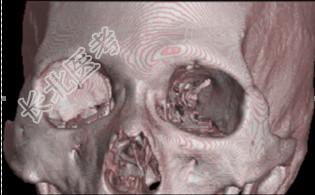

- [材料题] 患者男性,4岁,以“右眼外伤后视物不清8天”为主诉入院。眼部检查:右眼视力指数/0cm,左眼视力.0。右眼混合充血,角膜透明,KP(+),6点钟方位角膜缘可见2mm裂伤口,已闭合;前房中等深度,房水闪光(+);虹膜表面纹理清晰,无前后粘连,6点钟方位可见穿通孔;瞳孔圆,直径3mm;晶状体混浊;眼底无法窥视。左眼未见明显异常。眼眶X线检查结果见图155,CT检查结果见图156(平扫)和图157(三维成像)。

图155